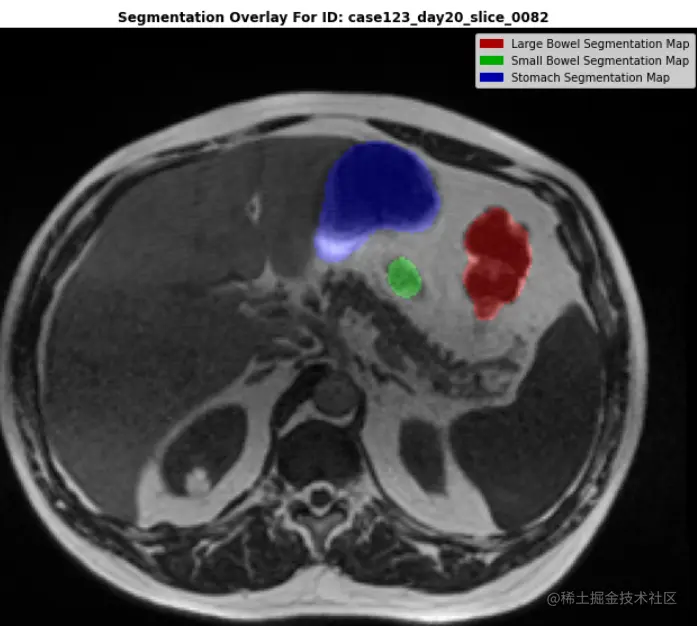

DEMO_ID = "case123_day20_slice_0082"

print(f"\n\n... LET'S PLOT THE IMAGE WITH AN RGB SEGMENTATION MASK OVERLAY ...\n")

plt.figure(figsize=(12,12))

plt.imshow(seg_overlay)

plt.title(f"Segmentation Overlay For ID: {demo_ex.id}", fontweight="bold")

handles = [Rectangle((0,0),1,1, color=_c) for _c in [(0.667,0.0,0.0), (0.0,0.667,0.0), (0.0,0.0,0.667)]]

labels = ["Large Bowel Segmentation Map""Small Bowel Segmentation Map""Stomach Segmentation Map"]

plt.legend(handles,labels)

plt.axis(False)

plt.show()